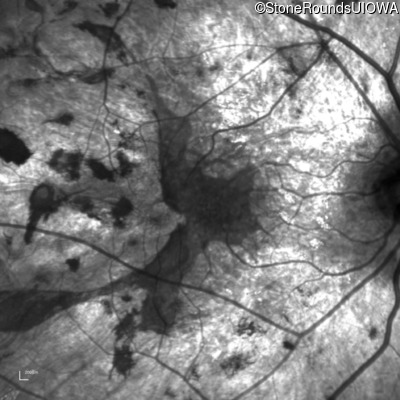

Age at visit: 35 years

This 35-year-old man has trouble in low light and when moving around in busy places. He first reported trouble seeing in low light at age 13. His maternal grandfather was similarly affected.